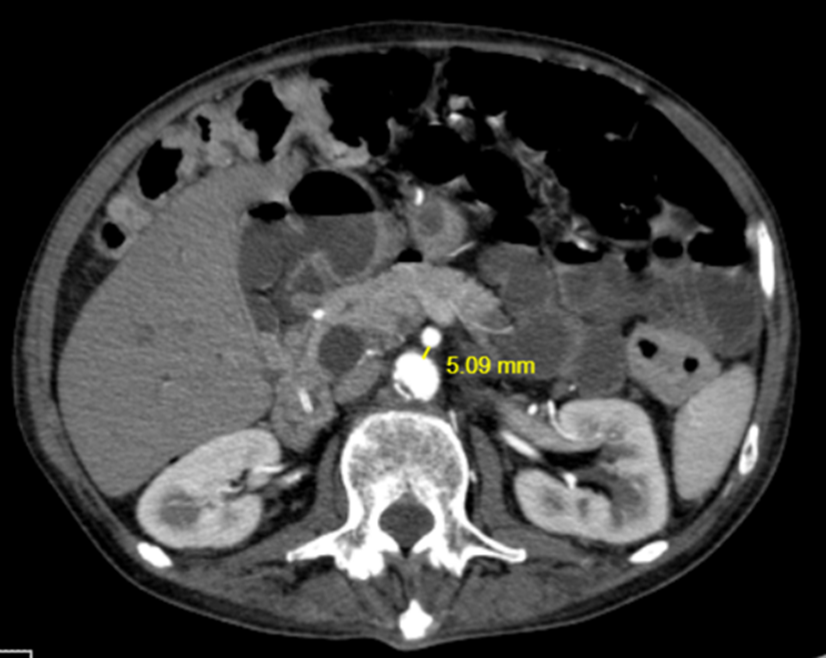

Initially, x-ray findings show gastric or gastroduodenal distention and a paucity of distal bowel gas [5]. Later, tomographic images include compression of the third part of the duodenum with proximal dilatation of the same and the duodenum. Through a deeper review of the literature, we found the normal parameters needed to take into consideration in the images’ review. Firstly, an aortomesenteric angle between 25°-60° and secondly, a distance between the AA and the SMA of 10 to 20 mm. In sagittal slices, Wilkie’s syndrome is defined as an aortomesenteric angle less than 22° (Figure 1) and in axial slices an aortomesenteric distance less than 10 mm (Figure 2) [2,5]. CT angiography provides the added benefit of thin (1-mm) slice thickness and multiplanar 3D reconstructions which allow for more precise evaluation of the aorto-mesenteric angle and aortomesenteric distance [5].

Figure 1. CT with IV contrast, axial section showing a reduced aortomesenteric distance of 5 mm.